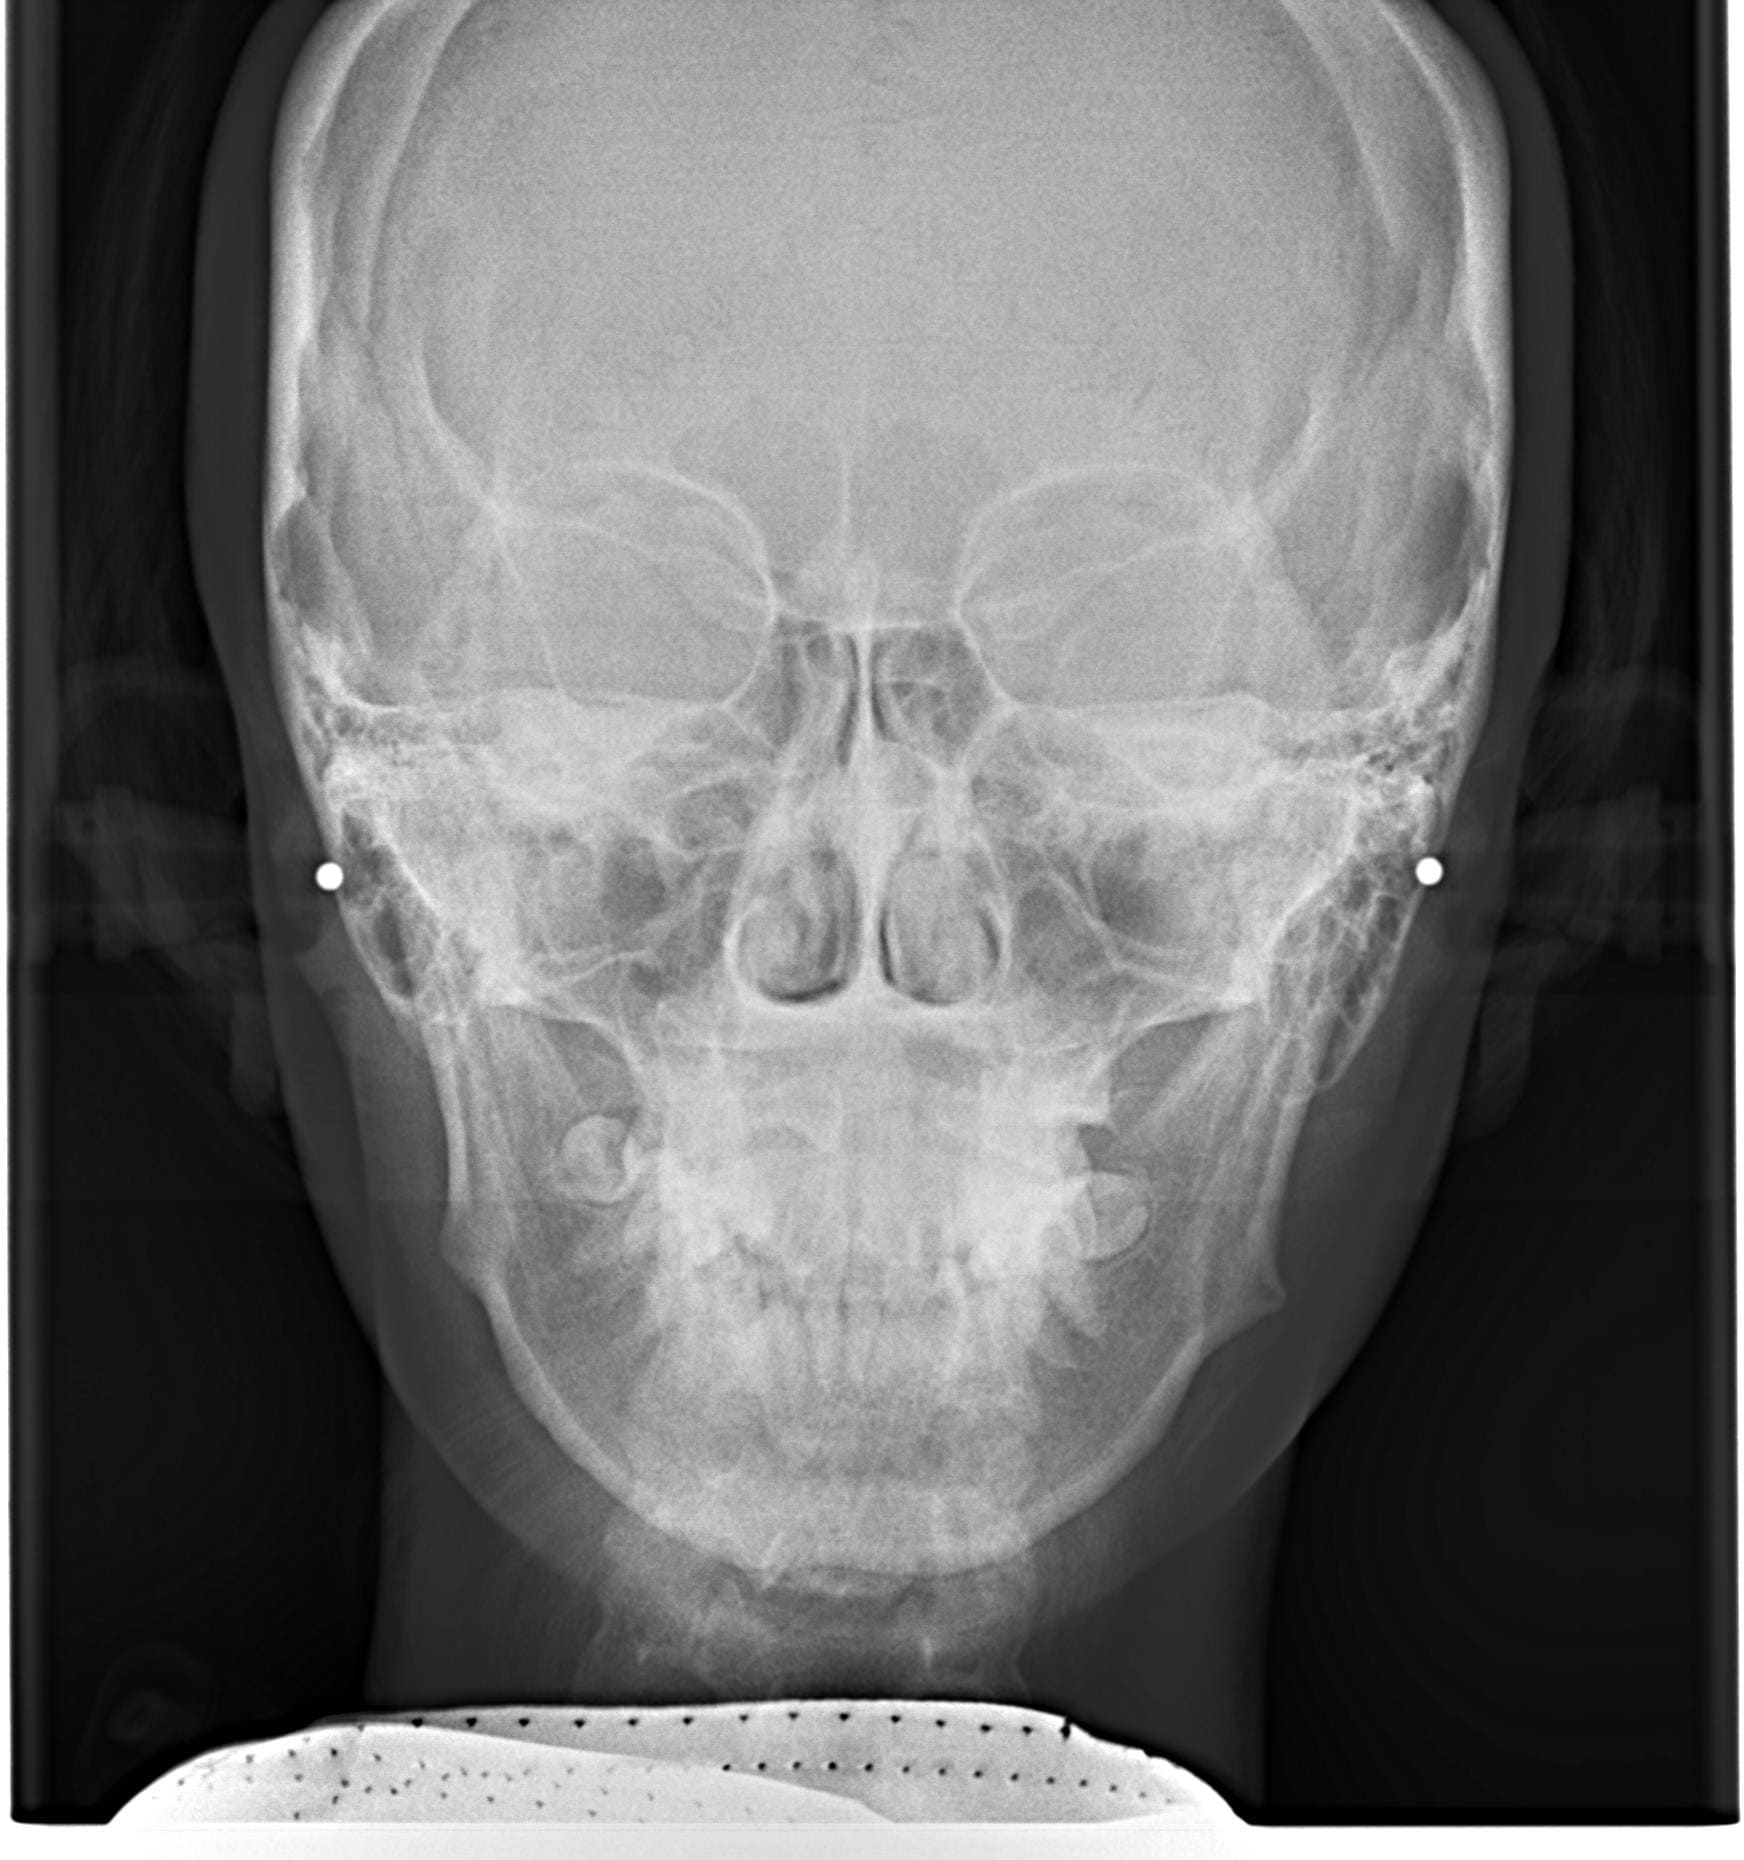

| 年齢・性別 | 21歳 |

|---|---|

| 主訴 | 叢生が気になる・前歯に埋伏歯がある |

| 治療期間・回数 | 6ヶ月 |

| 費用 | 935,000円 |

| 上顎の左側3番が埋伏していたため、上顎左右の3番および親知らずを抜歯し、矯正治療を行いました。 治療開始からおよそ6ヶ月で歯列が整い、審美的にも機能的にも良好な結果が得られた症例です。 |